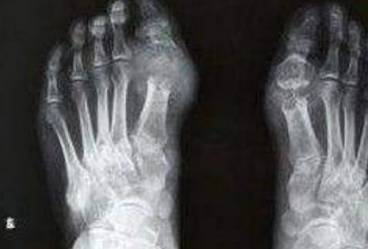

痛风是由于体内尿酸积聚过多、无法正常排出引起的,不仅给我们身心造成了巨大痛苦,还带来了生活上的很多不便。就连饮食都要倍加小心,生怕一不小心就吃到高嘌呤食物。